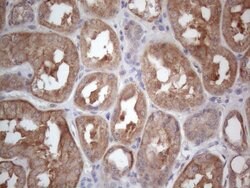

MTF1 Monoclonal Antibody for Western Blot, IHC (P)

| Immunohistochemistry (Paraffin), Western Blot | |